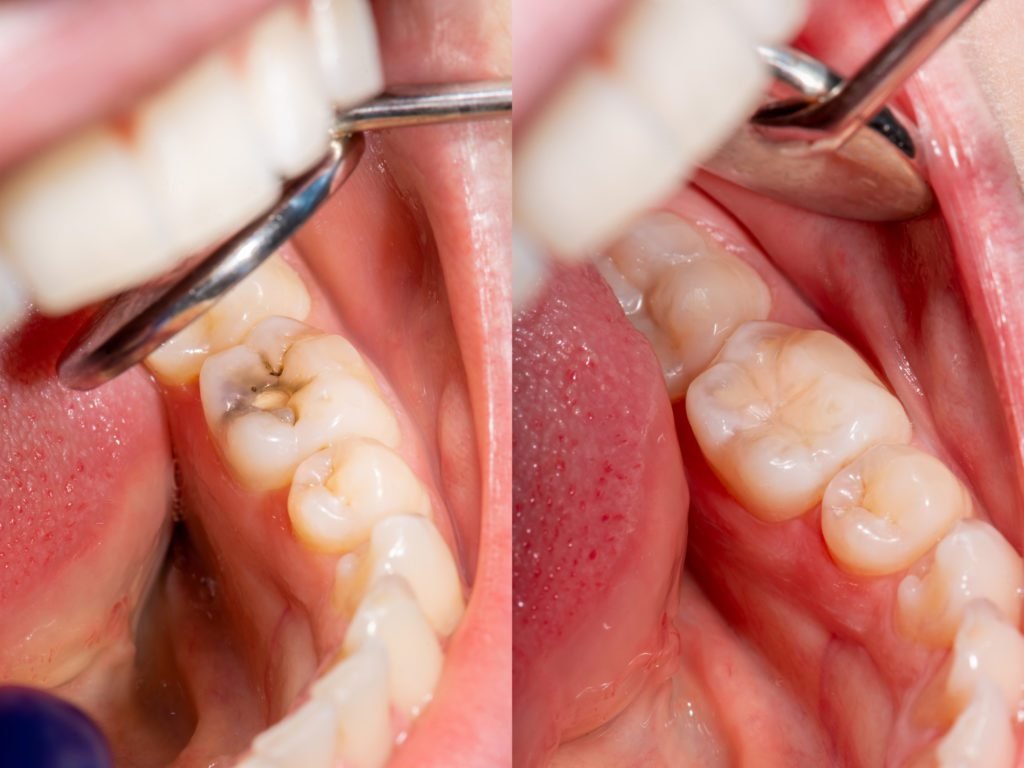

Durable, tooth-colored fillings to repair cavities and prevent decay.

Tooth Filling | Restore Cavities with Natural-Looking Results

Khan Dental Care offers high-quality tooth fillings that blend naturally with your teeth, repairing cavities and preventing further decay or damage.